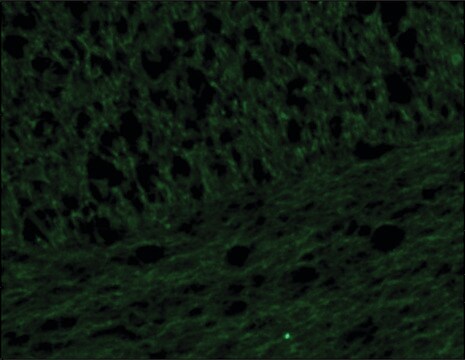

immunoblotting: 0.3-0.6 μg/mL using rat brain extract, immunofluorescence: 10-20 μg/mL using human bone marrow neuroblast SHSY5Y cell line, immunohistochemistry: 10-20 μg/mL using heat-retrieved formalin-fixed, paraffin-embedded human brain sections

Anti-Neurofilament 160 antibody has been used in immunoblotting, Immunohistochemistry, Immunofluorescence